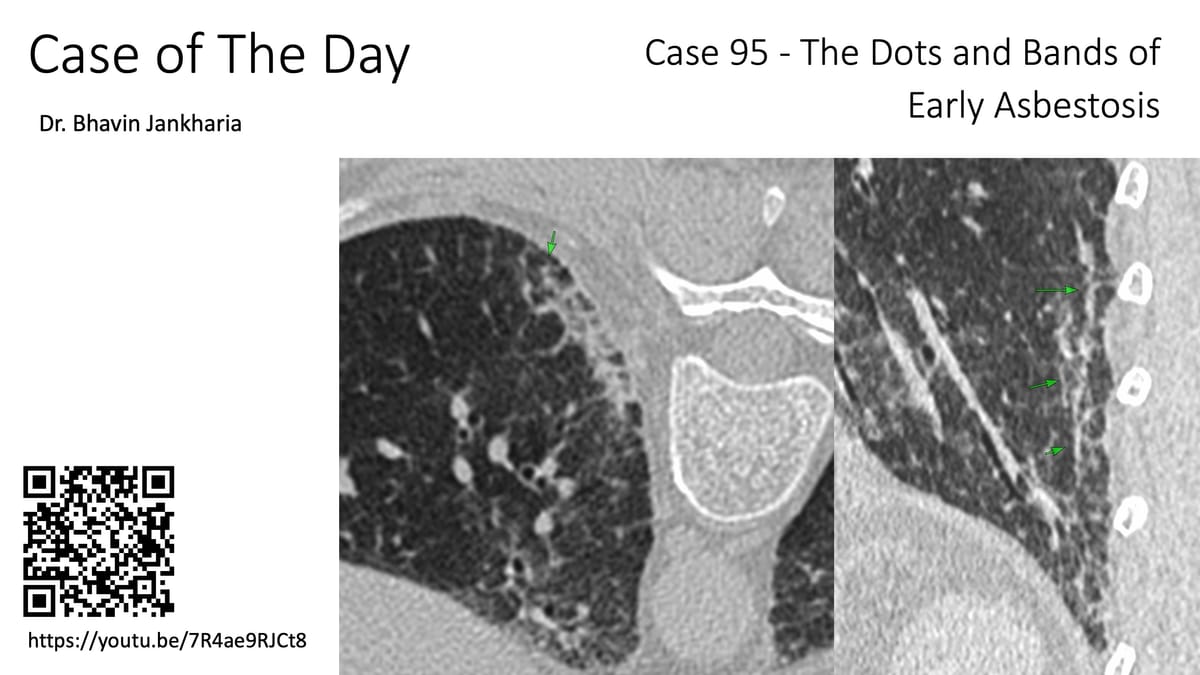

33-years old with scleroderma and scleroderma ILD with a fibrotic non-specific interstitial pneumonia (NSIP) pattern.

The upper lobes show interstitial lesions, typically considered to be part of the NSIP pattern.

A recent Japanese paper introduces the concept of FANO - faint amorphous nodular opacities - first described with asbestosis, which are seen typically in the anterolateral non-dependent upper lobes and most commonly associated with an NSIP pattern and are known to progress and likely represent early-stage interstitial disease.

This brings to focus the likelihood that the early stage scleroderma ILD cases I have shown earlier have also likely been FANO lesions.